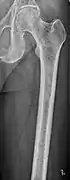

Multiple myeloma in the upper arm

Femur with multiple myeloma lesions

Same femur before myeloma lesions for comparison